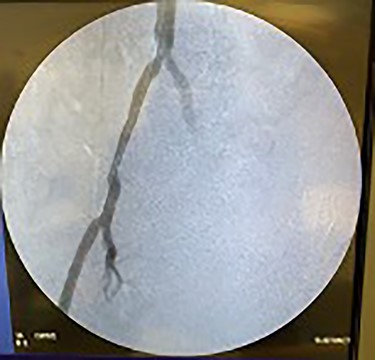

Catheter arteriogram results showed significant occlusion of the left iliac artery (Figs 3 and 4), the right iliac artery (Fig. 1), as well as the distal abdominal aorta (Fig. 2). There were numerous collateral vessels noted, indicating the presence of long-standing proximal stenosis (Fig. 1). The decision was made to use angioplasty to help widen the areas of stenosis. An 8 mm × 40 mm Passeo balloon was advanced from the right femoral artery into the left iliac artery (Fig. 7) and insufflated to 6 mmHg (Fig. 6). The balloon was allowed to remain expanded for 1 min and then was deflated. Next, the distal aorta was repaired in a similar fashion. The balloon was advanced into the distal aorta from the right femoral access and insufflated to 12 mmHg (Fig. 8). The balloon was allowed to remain expanded for 90 s.

Fluoroscopy showing dilation of the distal aorta post-angioplasty.